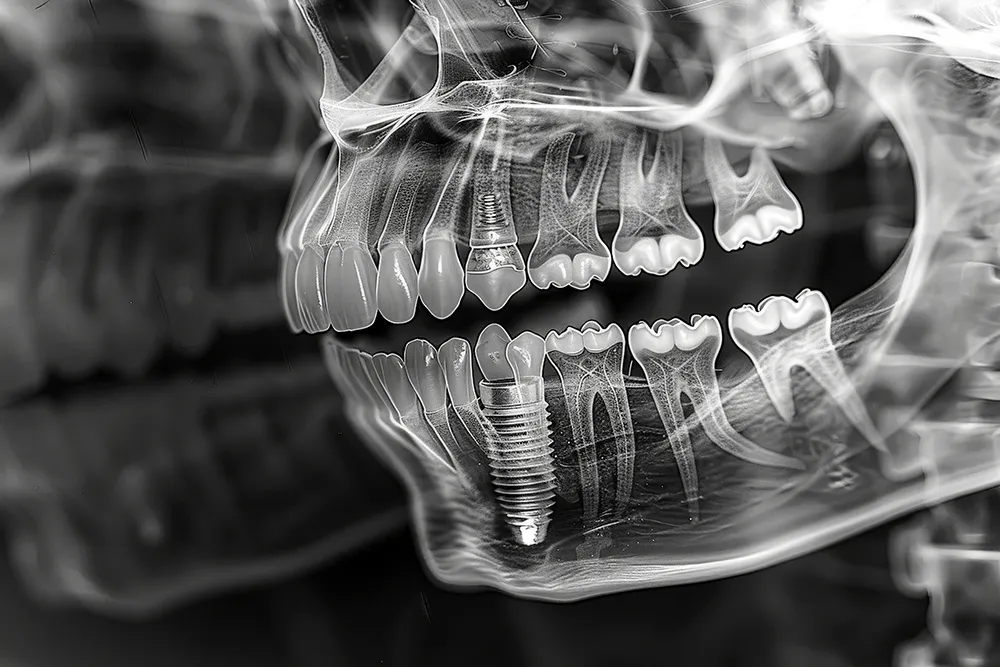

임플란트 1차 수술 과정

임플란트 1차 수술은 치아 뿌리를 대체할 금속 기둥을 잇몸 뼈에 심는 과정입니다. 먼저, 환자의 구강 상태를 살펴보고, X-ray나 CT 스캔을 통해 적절한 위치를 선정합니다. 수술 당일에는 국소 마취를 시행하며, 잇몸을 절개한 후 잇몸 뼈에 구멍을 뚫어 임플란트 기둥을 삽입합니다. 수술 후에는 잇몸을 봉합하고 보호 장치를 씌워줍니다. 이 과정은 대개 1~2시간 정도 소요됩니다.